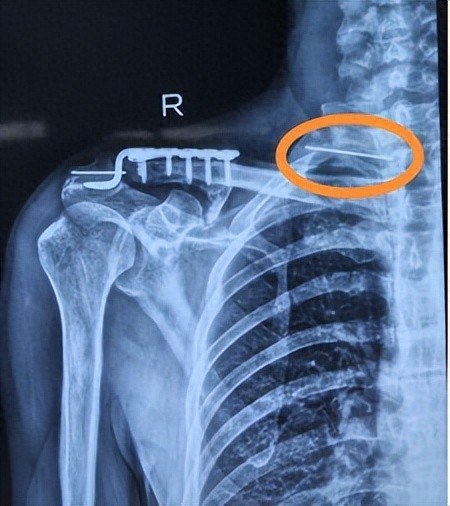

60岁的张先生,5年前在外院接受锁骨手术后,体内留置的固定钢针在1年前复查时被发现已断裂并移位。在辗转多地求医无果后,张先生来到了西安市红会医院胸部外科就诊。影像检查显示,断裂的钢针尖端已扦插入胸椎锥体,紧邻第二肋骨,这种情况可能会引起不良后果,急需尽快处理

胸部外科医疗团队立即启动了全科病例讨论。胸部外科景宝利主任表示,断裂的钢针如同“定时炸弹”,必须尽快手术取出。考虑到断裂钢针的具体位置,位于第一肋骨和第二肋骨之间,紧邻第二肋骨上缘,且部分尖端已扦插入锥体,传统开放手术创伤大、找寻钢针难度高、风险高且恢复慢。因此,团队最终决定采用“胸腔镜下经胸腔内部异物取出术”的微创方案,既能精准解决问题,又能最大限度地减少手术创伤。

胸腔镜下移位断裂的钢针